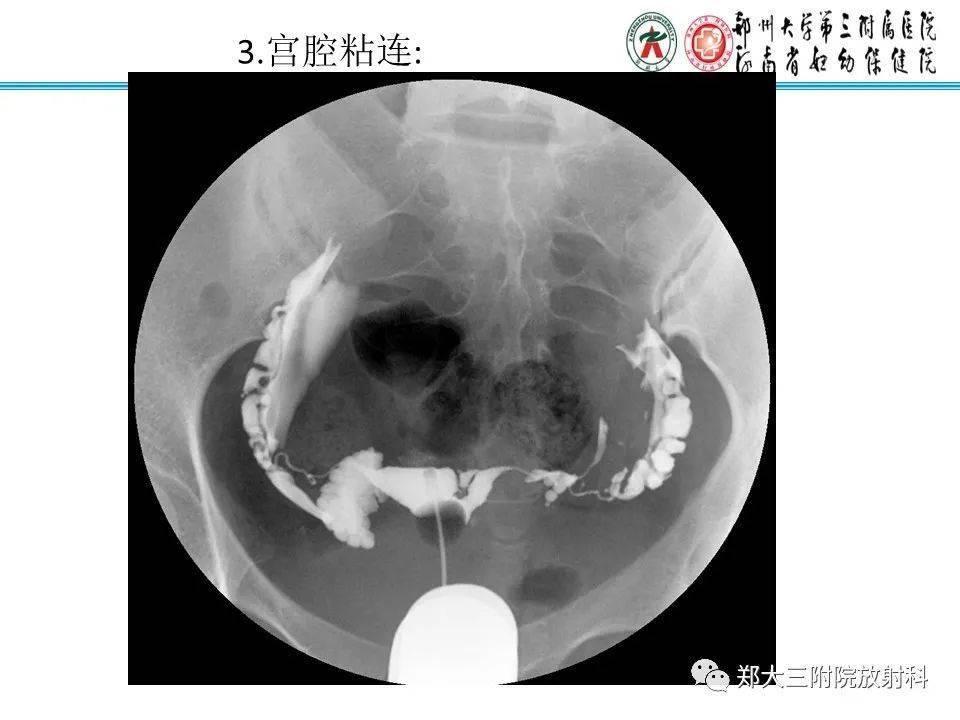

子宫输卵管造影检查的临床应用

图片尺寸960x720